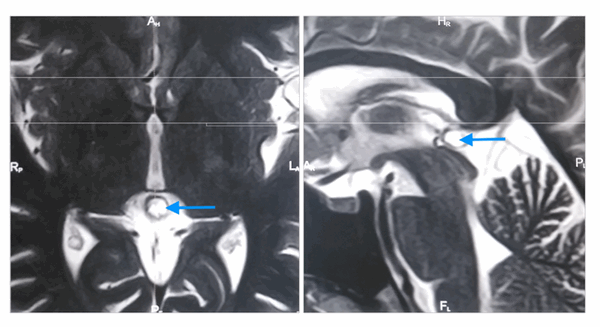

![]()

Киста шишковидной железы с типичным гиперинтенсивным сигналом на МРТ (Т2 ВИ) (отмечена синей стрелкой). Слева: аксиальная томограмма, справа – сагиттальная

На МРТ наблюдаются следующие признаки:

- Типичный изо- или гипоинтенсивный сигнал по сравнению с паренхимой головного мозга

- В 55–60% случаев гиперинтенсивный сигнал по сравнению с ликвором

- Сигнал обычно однородный

- Сигнал высокой интенсивности

- Обычно слегка менее интенсивный по сравнению с ликвором

- Сигнал высокой интенсивности, который часто не подавляется полностью

- Рестрикция диффузии отсутствует

- Примерно 60% кист накапливают контраст

- Накопление контраста в большинстве случаев происходит в виде тонкого (меньше 2 мм) и ровного «ободка» (полного или неполного)

- Возможно диффузное контрастное усиление жидкостного содержимого кисты препаратами на основе гадолиния в отсроченной фазе (60–90 минут), вследствие чего киста становится похожей на солидное объемное образование

- Редко может обнаруживаться нетипичное узловое контрастное усиление, также могут определяться признаки кровоизлияния в кисту